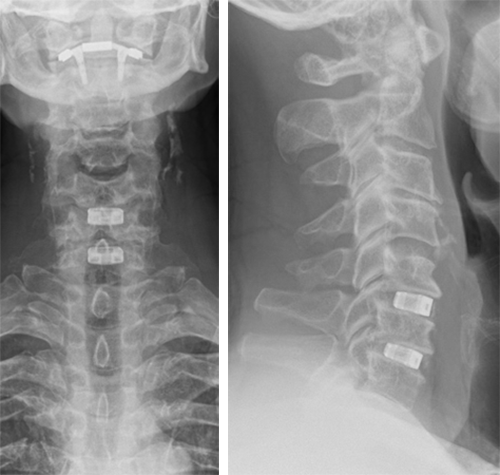

Surgical treatment

The patient underwent anterior decompression and fusion C5-6-7 with Conduit stand-alone cages C5-6-7. Restoration of lordosis C5-7 (Fig 7).